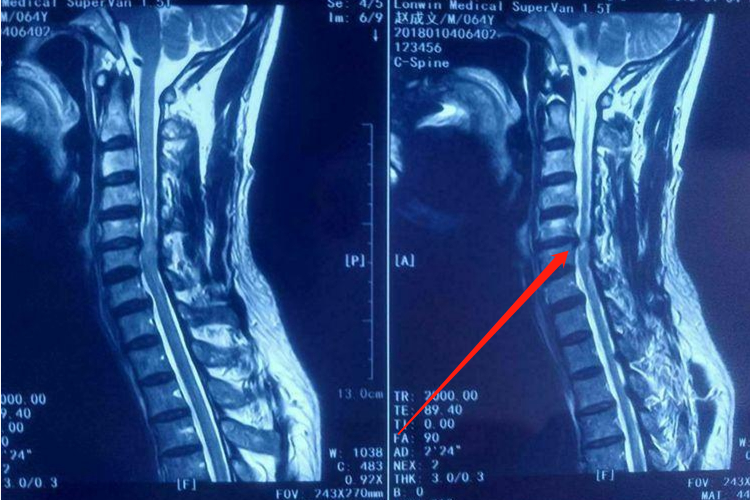

脊髓型颈椎病:患者先从下肢双侧或者单侧发沉、发麻开始,随之出现行走困难,下肢肌肉发紧,抬步慢,不能快步走,重者步态蹒跚。最明显的体征是四肢肌张力升高,下肢往往较上肢明显。CT平扫可见颈椎间盘突出,椎管明显受压。核磁共振检查可显示颈椎脊髓受压。